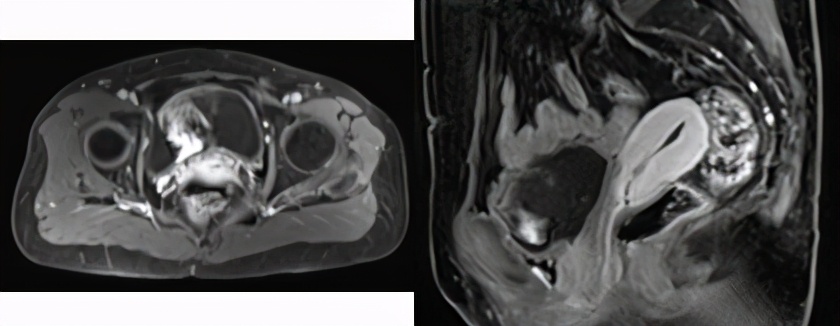

2013-02-18盆腔MRI示:宫颈占位,侵犯阴道后穹窿,盆腔淋巴结未见明显肿大。

治疗前MRI(2013.2)

放疗后MRI(2013.6)